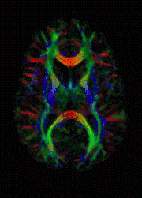

MRI de difusão, IRM de difusão, ou imagem de difusão por ressonância magnética é um método IRM ou MRI (do inglês magnetic resonance imaging, obtenção de imagens por ressonância magnética) que produz imagens in vivo de tecidos biológicos ponderadas com as características microestruturais locais da difusão de água. O campo de MRI de difusão pode ser entendido em termos de duas classes distintas de aplicação—MRI ponderada de difusão e MRI de tensor de difusão. MRI ponderada de difusão pode prover informação sobre danos a partes do sistema nervoso. MRI de tensor de difusão pode prover informação sobre as conexões entre as regiões do cérebro.

Na imagem ponderada de difusão (DWI, de diffusion weighted imaging), cada voxel de imagem (pixel tridimensional) tem uma intensidade na imagem que reflete uma única melhor medição da taxa de difusão da água naquele local. Esta medida é mais sensível a alterações iniciais após um acidente vascular cerebral que as medições com MRI tradicionais tais como taxas de T1 ou T2 de relaxamento de T2. DWI é principalmente aplicável quando o tecido de interesse é dominado por movimento de água isotrópica, e.g. substância cinzenta no córtex cerebral e os principais núcleos cerebrais—onde a taxa de difusão parece ser a mesma quando medida ao longo de qualquer eixo.